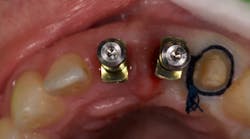

I began centering my consultation appointments on options that subsequently allowed patients to actually sell themselves on the implant treatment modality. I would present the tooth-replacement options of endo/core/crown, extraction/bridge, and extraction/implant ... and then I would explain the pros and cons of each. What I found is that patients overwhelmingly chose the root-replacement option—dental implants—over the old-school (drill-o-dontics) to reconstruct their missing tooth. Patients actually wanted an implant once they were armed with all the complete information they needed to make their decision. Having models on hand that show the difference between each option is highly effective, especially for those patients who are visual learners.

This is the paradigm shift in thinking that initiated big changes in my practice. In 2010, my little office restored 38 implant fixtures. By 2017, we were restoring closer to 200. What a difference! When patients began to realize they had treatment possibilities that may have a better long-term prognosis than the traditional replacement options, implants became a definite green light for them.